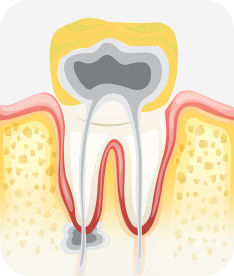

치아신경 염증

충치가 심해져 치아 뿌리까지 신경 염증이 발생함

신경소독

충치를 제거하고, 치아 뿌리 끝까지 신경관 내부의 염증 물질들을 제거하고 소독함

신경치료 완료

소독된 신경관을 생체친화적인 재료로 충전한 후 보철치료를 함

치수염 충치

밤에 잠을 이루지 못할 정도로 아프거나 찬 것과 뜨거운 것에 통증이 있을 수 있으며, 도중에 나은 것처럼 증상이 없어지는 경우도 있음. 치아의 경조직 뿐 아니라 치수까지 염증이 생긴 상태.

치료방법 신경치료, 크라운 등 보철치료